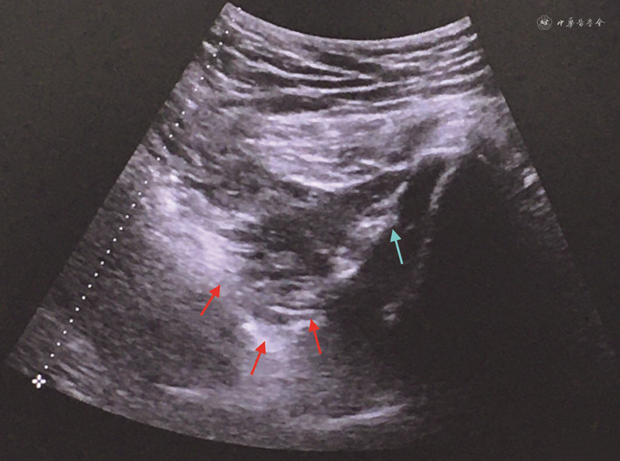

调整药物治疗方案+超声引导下盆底肌筋膜触发点和骨盆外肌筋膜触发点注射。药物治疗:盐酸度洛西汀肠溶胶囊20 mg、每晚1次+盐酸乙哌立松片50 mg、每日3次+洛索洛芬钠片60 mg、每日3次+强力天麻杜仲胶囊0.4 g、每日2次。超声引导下盆底肌筋膜触发点和骨盆外肌筋膜触发点注射:体表按压、触摸触发点,超声引导下避开重要血管神经进针到达触发点,患者有酸痛感,经以上双重定位后,先行干针触发点灭活,再局部注射混合溶液3 ml(复方倍他米松注射液1 ml+牛痘疫苗接种家兔炎症皮肤提取物注射液3.6 U+盐酸罗哌卡因注射液100 mg+甲钴胺注射液0.5 mg,生理盐水稀释至40 ml),同时在阴部神经管(Alcock管)处进行阴部神经阻滞。见图1。开始时每周治疗1次×4周(共4次),后隔周治疗1次×8周(共4次),再巩固治疗1次。患者共完成治疗9次,第1次治疗后疼痛即缓解20%,第2次后疼痛缓解40%;第3次治疗后疼痛强度缓解60%~70%、疼痛频率减少为原来的50%,疼痛范围减少。第7次治疗时疼痛缓解80%,自行停止口服药物。末次治疗时,日常活动疼痛NRS 1分,大小便症状明显缓解,结直肠肛门影响问卷(colorectal-anal impact questionnaire,CRAIQ-7)从治疗前的18.8分下降为12.5分,排尿影响问卷(urinary impact questionnaire,UIQ-7)从治疗前的29.2分下降为20.8分,膀胱过度活动症症状评分表(overactive bladder syndrome score,OABSS)从治疗前的3分下降为2分。查体骨盆内外的触发点压痛基本消失。

MPPS的治疗关键是灭活触发点并去除致病因素。对于非侵入治疗(物理治疗和手法治疗)无效的患者,应该行侵入性治疗(干针和注射)。用于触发点灭活和神经阻滞的注射药物主要是局部麻醉剂和皮质类固醇,有多量成功的文献报道。其机制是通过破坏肌肉绷紧带重构肌肉,增加血流量;另一假说是机械破坏骨骼肌纤维中异常收缩元件来中断过度活跃的反射弧[16]。有研究纳入了186例CPP患者,尽管完成全疗程的物理治疗后仍未完全缓解疼痛,进行超声引导下的神经阻滞和触发点注射灭活,进一步缓解了疼痛并改善了盆底功能[17]。由于超声可实时呈现目标区域的软组织(如肌肉、韧带)和血管结构,能实时监测进针轨迹和注射药物的扩散,与盲穿相比,超声引导下的操作具有精准性更高、效果更确切的优势。超声引导技术操作简便易行、无放射性污染,在慢性疼痛介入治疗领域的应用逐渐增多[18]。本例患者采用手法触诊和患者对针刺的疼痛反应定位触痛点,结合超声对局部解剖的识别,对盆底肌触发点、阴部神经及躯干部肌肉的触发点进行了逐一灭活,前后共治疗9次,患者治疗期间停止了止痛药物的使用,取得了满意的止痛疗效,进一步印证了最初的诊断,对于难治性的盆底肌筋膜痛也有了更深层次的认识。